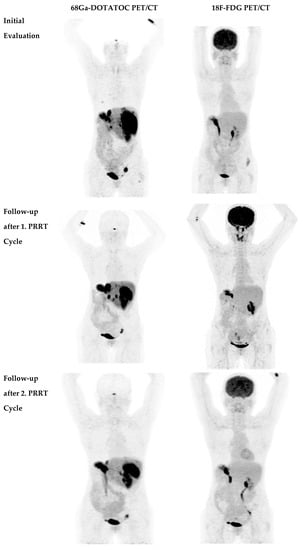

2.2. Disease Course after Second PRRT Course

- Nilica, B.; Waitz, D.; Stevanovic, V.; Uprimny, C.; Kendler, D.; Buxbaum, S.; Warwitz, B.; Gerardo, L.; Henninger, B.; Virgolini, I.; et al. Direct comparison of 68Ga-DOTA-TOC and 18F-FDG PET/CT in the follow-up of patients with neuroendocrine tumour treated with the first full peptide receptor radionuclide therapy cycle. Eur. J. Nucl. Med. Mol. Imaging 2016, 43, 1585–1592. [Google Scholar] [CrossRef]